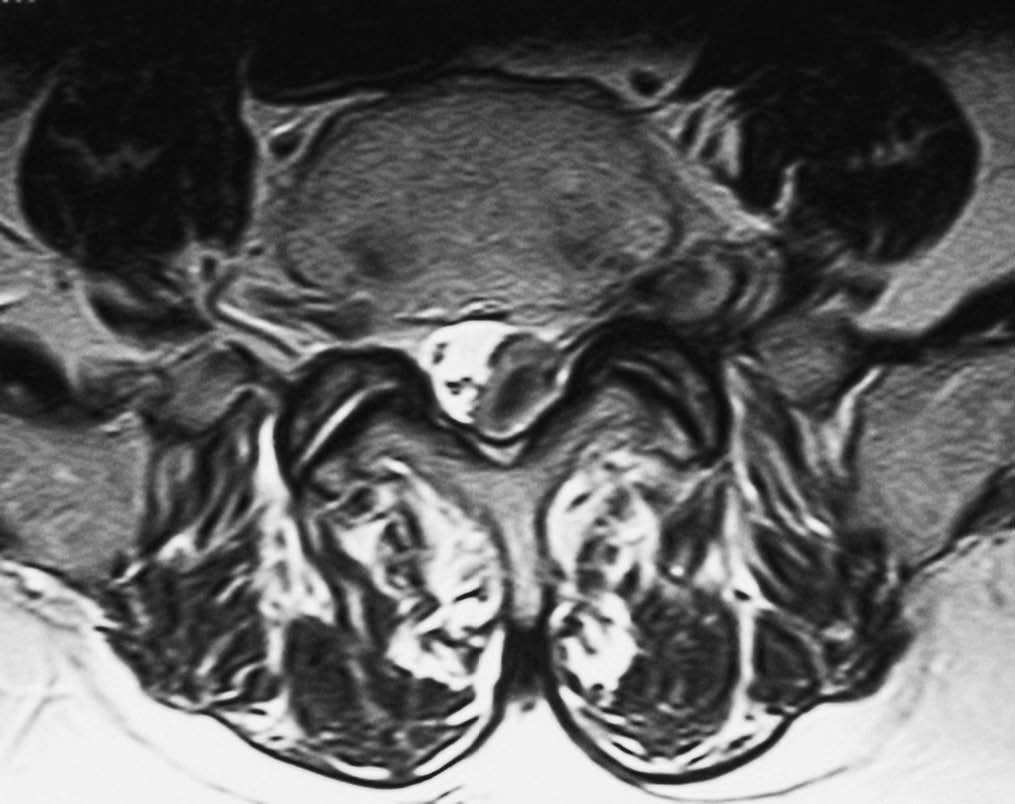

Fig. 1--RM secuencia TSE pT2. Corte axial. Lesión en canal, foramina y espacio extraforaminal con "morfología en reloj de arena". La raíz nerviosa correspondiente se aprecia separada de la hernia en el espacio extraforaminal. Respecto al músculo psoas la periferia de la lesión es discretamente hiperintensa y su centro isointenso.